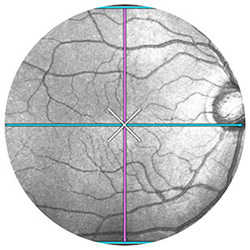

Вбудований скануючий лазерний офтальмоскоп значно сприяє якості сканування та простоті використання. Забезпечення відстеження сітківки у режимі реального часу дозволяє точно контролювати обстеження.

Швидке та чітке відстеження

Скануючий лазерний офтальмоскоп точно слідкує за обстеженням та автоматично підлаштовує позицію сканування під те саме положення, що було під час попереднього сканування. Для надійного порівняння програмне забезпечення автоматично обирає однакові параметри сканування.

АВТОМАТИЧНЕ НАЛАШТУВАННЯ ВИСОКОЇ ЯКОСТІ ЗОБРАЖЕННЯ

Часом, мимовільні рухи очей під час дослідження неминучі. З вбудованим скануючим лазерним офтальмоскопом з технологією відстеження сітківки у реальному часі система дозволяє встановити ту саму позицію сканування автоматично. В результаті трекінг сітківки Xephilio OCT-значно знижує артефакти руху та таким чином забезпечується постійна висока якість зображення.